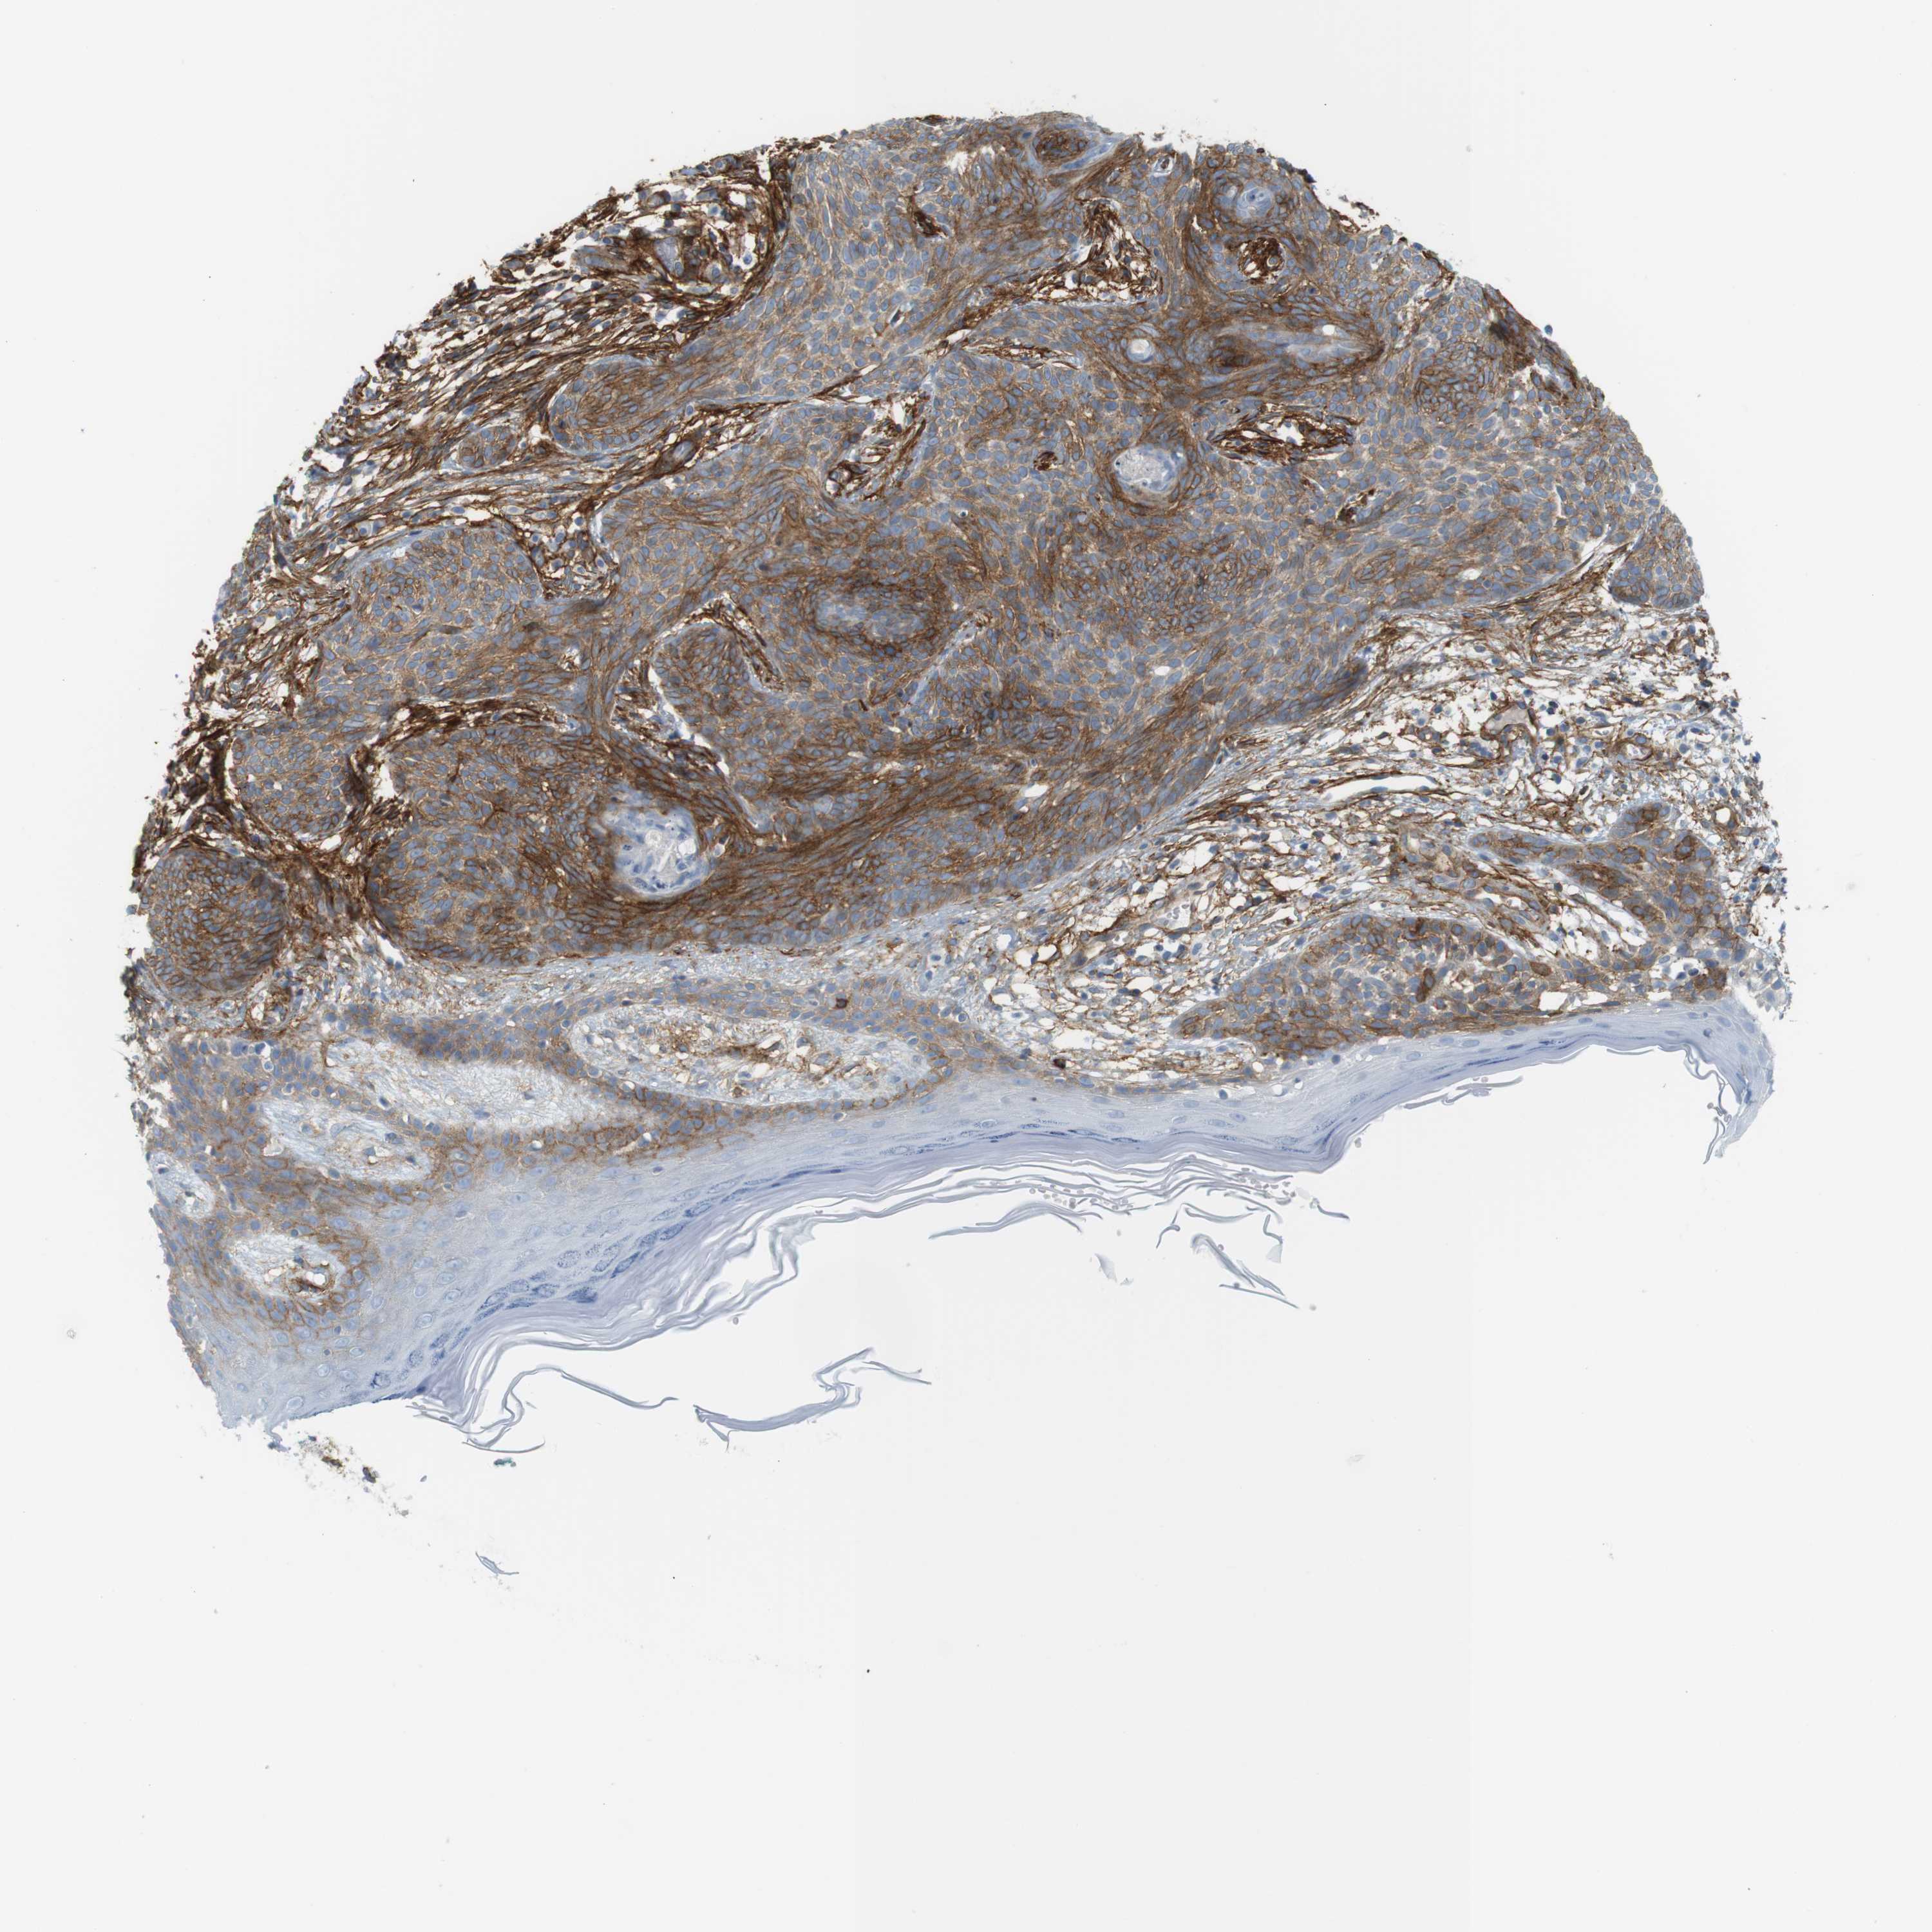

SKIN CANCER - Protein expressioni

A mouse-over function shows sample information and annotation data. Click on an image to view it in a full screen mode. Samples can be filtered based on level of antibody staining by selecting one or several of the following categories: high, medium, low and not detected. The assay and annotation is described here.

Antibody stainingi

Antibody staining in the annotated cell types in the current human tissue is reported as not detected, low, medium, or high, based on conventional immunohistochemistry profiling in selected tissues. This score is based on the combination of the staining intensity and fraction of stained cells.

Each image is clickable and will lead to virtual microscopy that enables deeper exploration of all samples and also displays staining intensity scores, fraction scores and subcellular localization as well as patient and tissue information for each sample.

Antibody CAB008973

Antibody CAB012962

Staining

High

Medium

Low

Not detected

Intensity

Strong

Moderate

Weak

Negative

Quantity

>75%

75%-25%

<25%

None

Location

Nuclear

Cytoplasmic/membranous

Cytoplasmic/membranous,nuclear

Squamous cell carcinoma, NOS